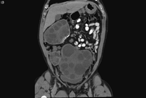

Robotic right segmental hepatectomy for the treatment of a giant hepatic hemangioma—a case report

Christoforos Efthimiadis and others

Journal of Surgical Case Reports, Volume 2017, Issue 6, June 2017, rjx118, https://doi.org/10.1093/jscr/rjx118